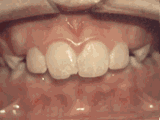

Missing lateral incisors

This patient's lateral incisors were congenitally missing. She had braces for twenty months to move the teeth into the correct position, then the missing teeth were replaced with bonded "Maryland" bridges.